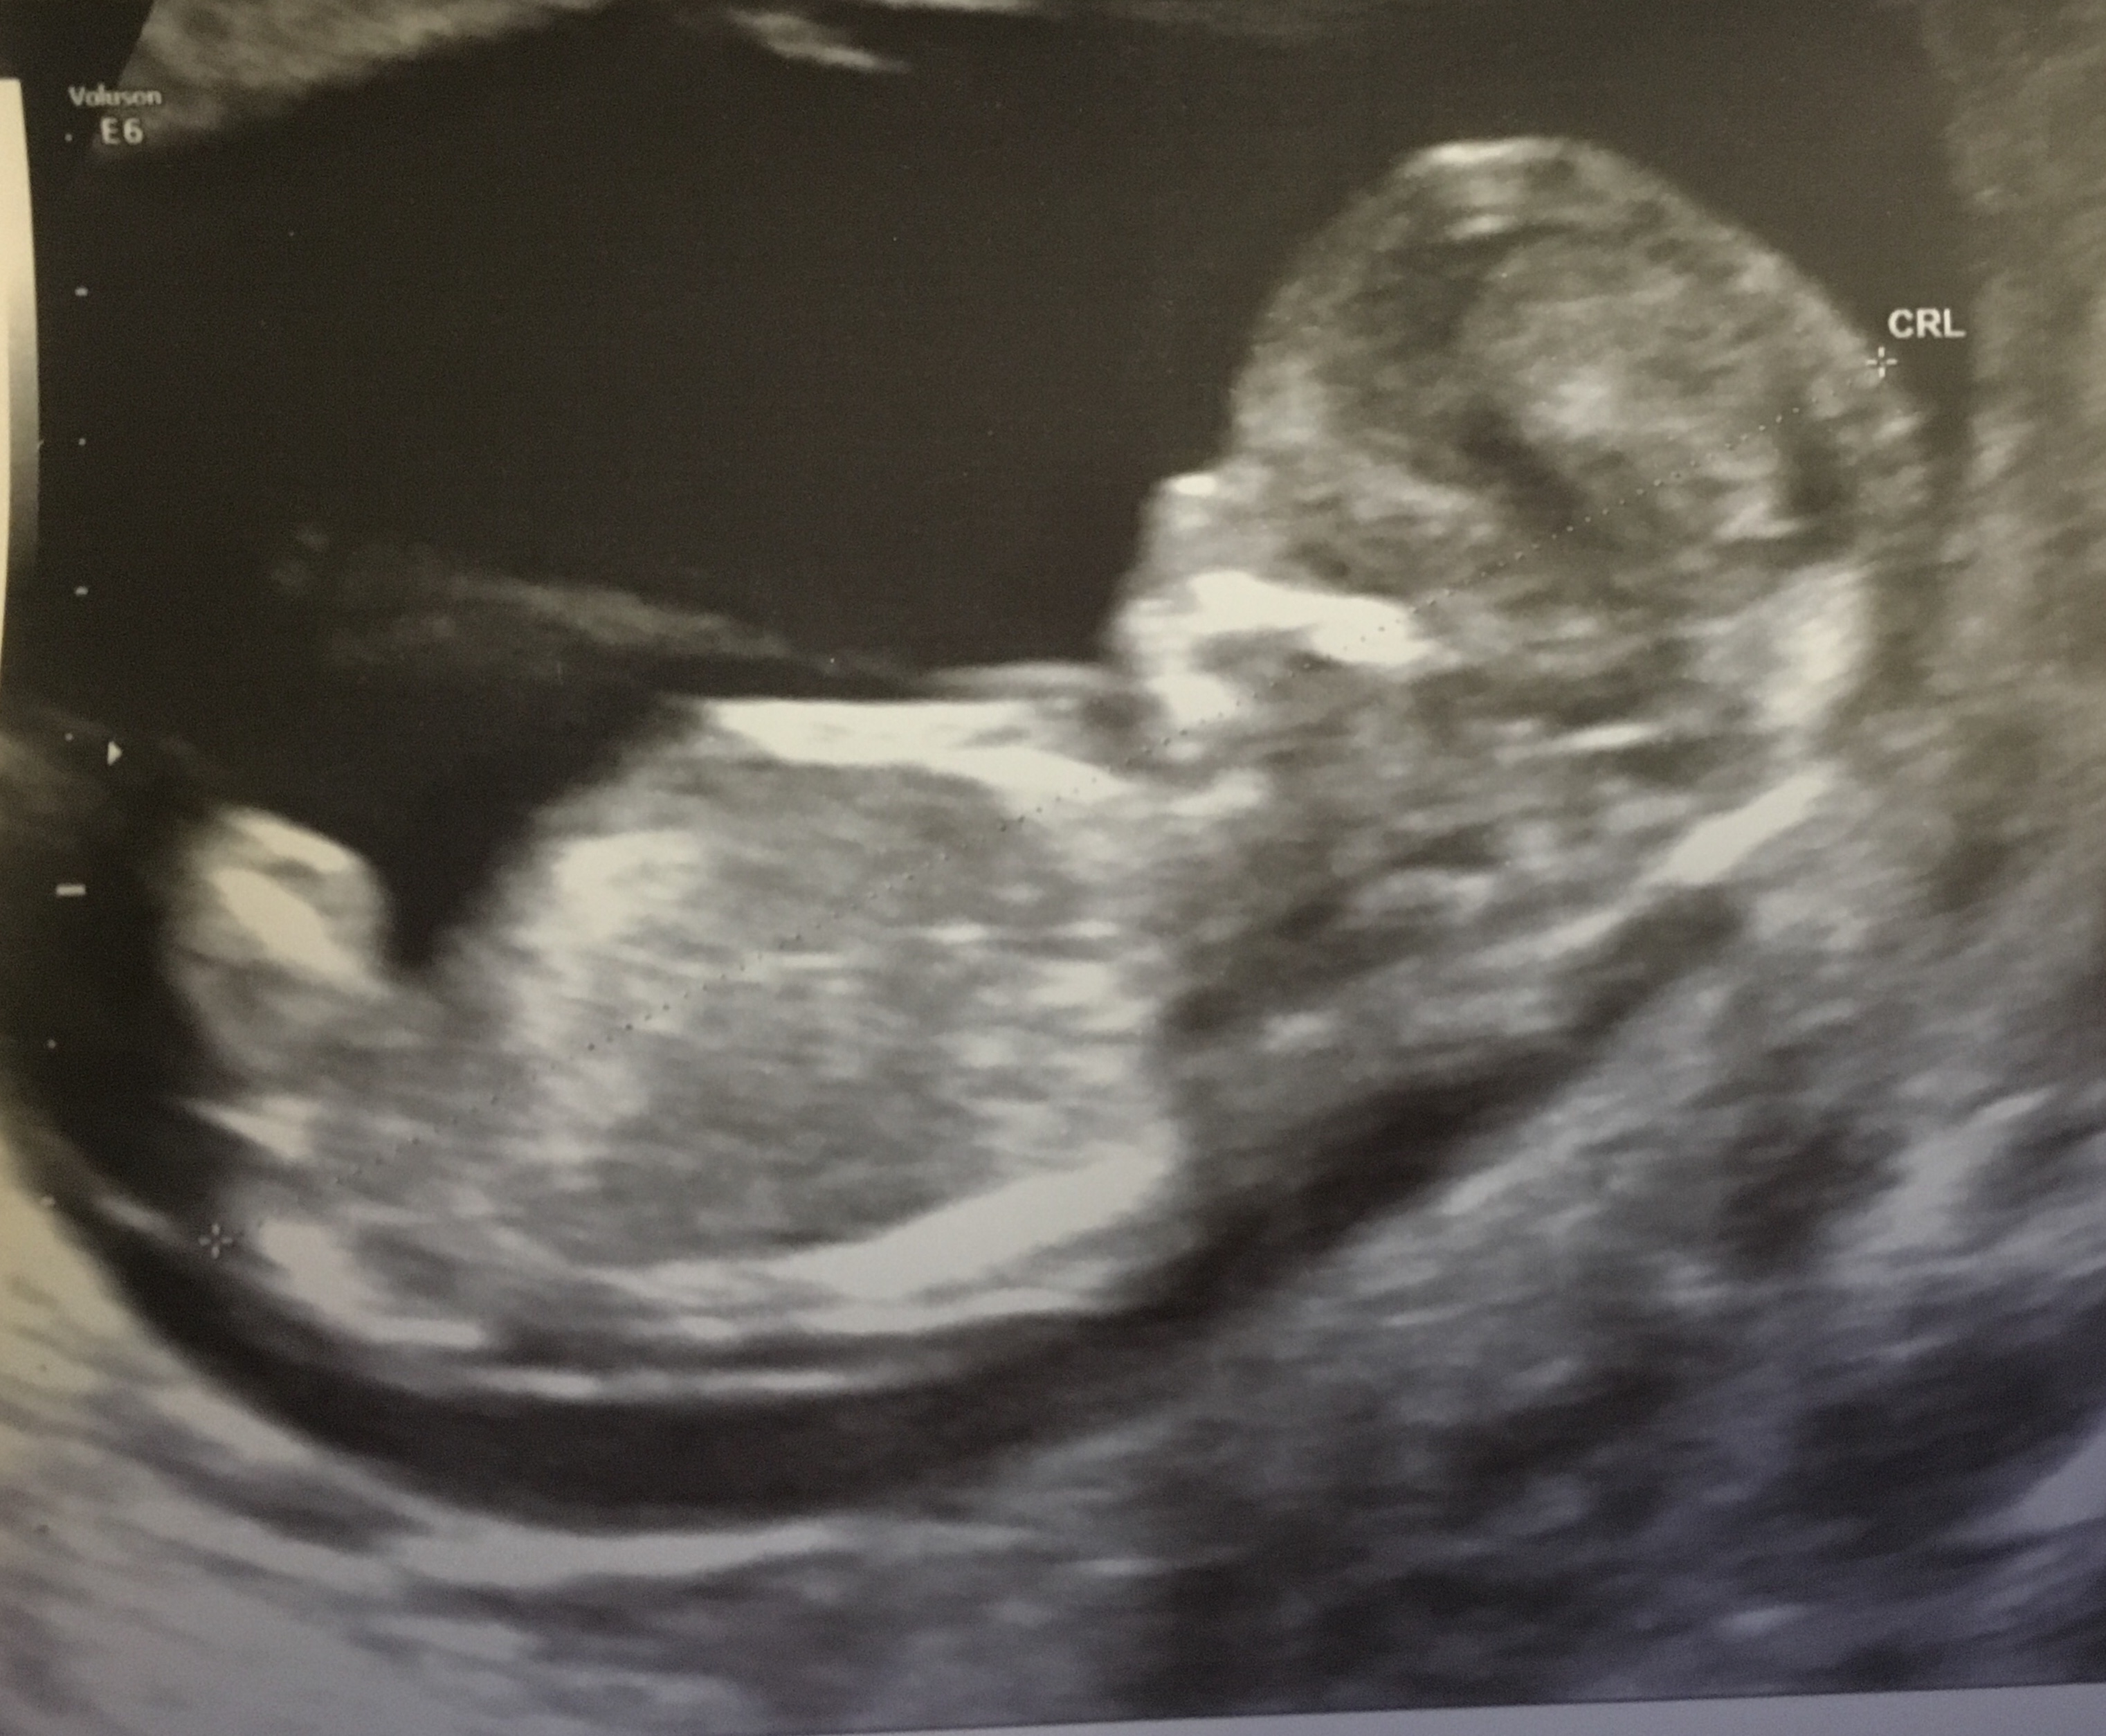

maybe boy? but unsure what I am looking at is the nub. cute little bub though xo

Lean boy?